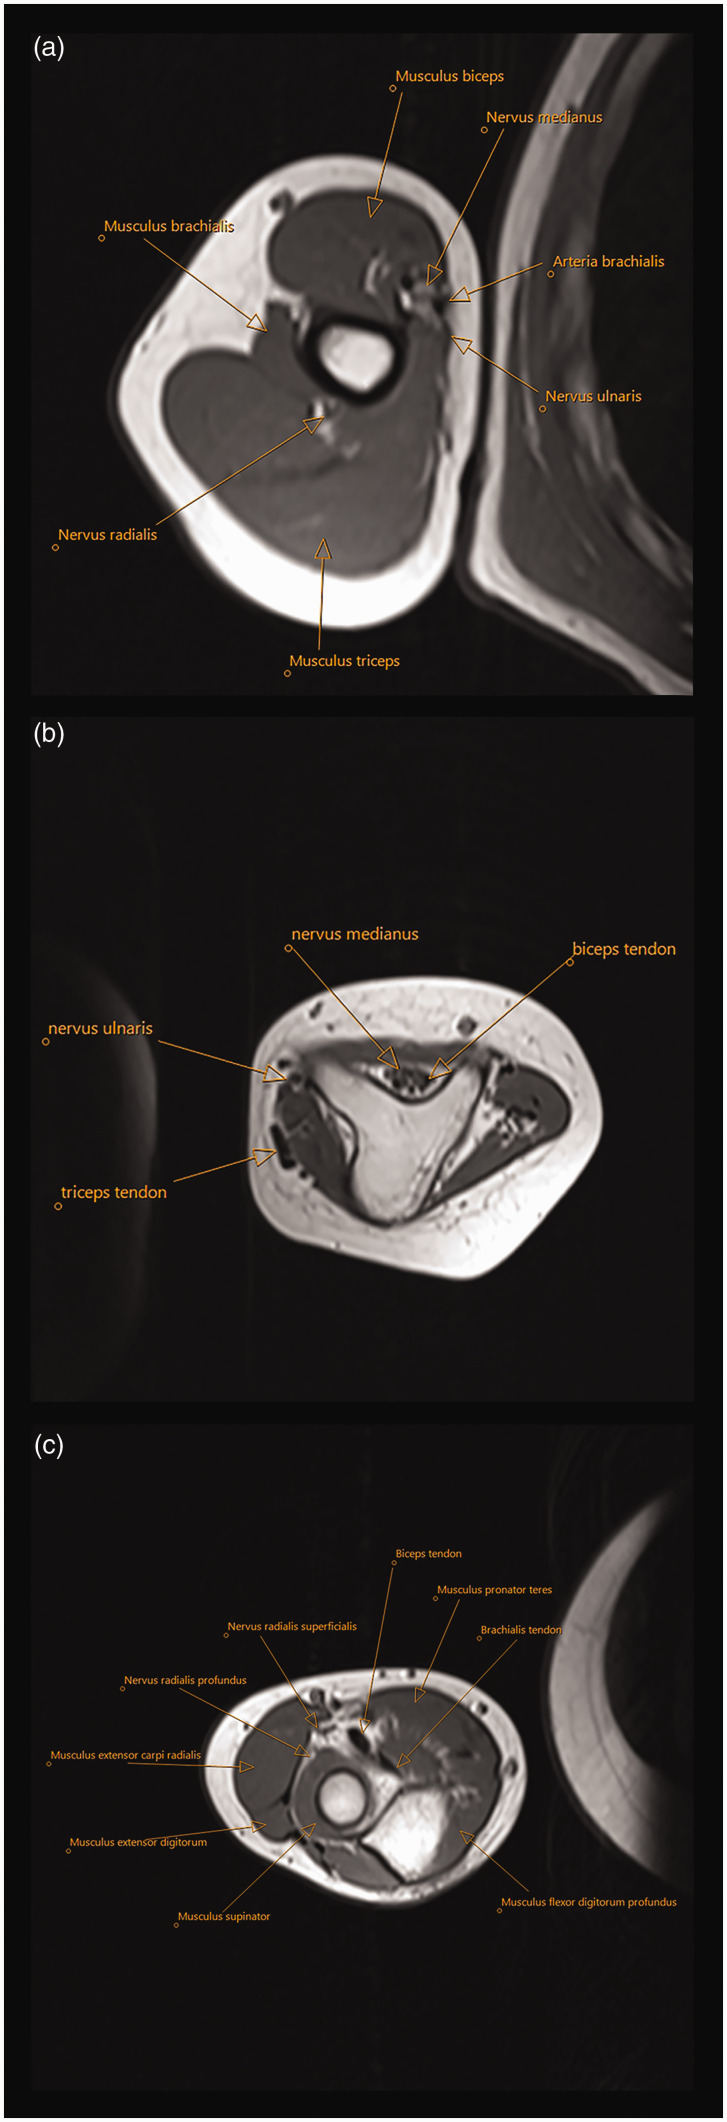

尺骨缺角是一种非常罕见的影响整个肢体的单侧先天性上肢畸形(CULA)。由于复杂性和多层次的累及,治疗仍然很困难。根据结构化的参数列表,对来自七个欧洲中心的24例尺骨重复,桡骨缺失和多指畸形进行了审查。首次问诊时,中位年龄为8个月(1-178),17例患者肩关节活动度良好,6例患者肩关节活动度较差,中位被动肘关节活动度为20°(0°-90°)。22/24例患者静息腕关节位屈曲。在拉伸和夹板后,肘关节手术包括11例患者的外侧近端尺骨切除术和6例患者的肌肉转移,分别改善被动运动和增加主动肘关节运动。8例患者进行了肌腱转移,23例患者进行了极化或伪极化。总体而言,患者术后表现出可接受的功能。提出了治疗这种严重CULA的指南。证据等级:四级。

Ulnar dimelia is a very rare unilateral congenital upper limb anomaly (CULA) affecting the whole extremity. Treatment remains difficult because of the complexity and multi-level involvement. Twenty-four cases with duplicated ulna, absent radius and polydactyly from seven European centres were reviewed according to a structured list of parameters. At first consultation, median age 8 months (1-178), the shoulder movement was good in 17 patients or poor in six, and the median passive elbow range of motion was 20° (0°-90°). The resting wrist position was flexed in 22/24 patients. Following stretching and splinting, elbow surgery included resection of the lateral proximal ulna in 11 patients and muscle transfers in six to improve passive movement and increase active elbow motion, respectively. Tendon transfers were performed in eight wrists and a pollicization or pseudo-pollicization in 23 patients. Overall, patients demonstrate acceptable function postoperatively. Guidelines for treatment of this severe CULA are presented.Level of evidence: IV.